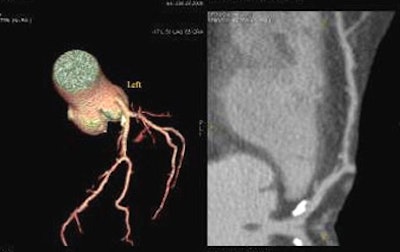

![]() |

| A 52-year-old firefighter with abnormal treadmill results underwent gated coronary calcium scan demonstrating a score of 132. The subject then underwent coronary CTA, which demonstrated a stenosis of approximately 70% in the midleft anterior descending artery. After percutaneous transluminal angioplasty and stenting the patient returned to work. |